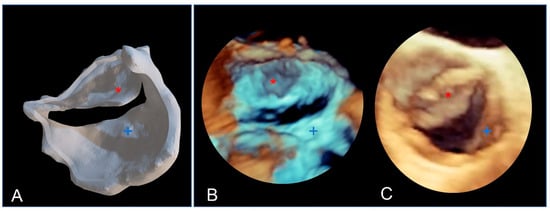

Due to their porous structure, the TPU and TPE models exhibit interesting echogenic properties. We compared the echogenic rendering with in situ images of the same valve (refer to Figure 9 and Figure 10). The valve structure was accurately depicted in both 3D and 2D views. Notably, the cusp in situ thickness measurements align with the model’s 0.3 mm thickness.

The bicuspid aortic valve in a similar face-plan view. (A) View of the 3D printed model. (B) A 3D ultrasound view of the immersed model (with two thin aortic cusps marked with * and +). (C) A 3D ultrasound in situ view of the same valve in the patient, showing both cusps (+ and *).